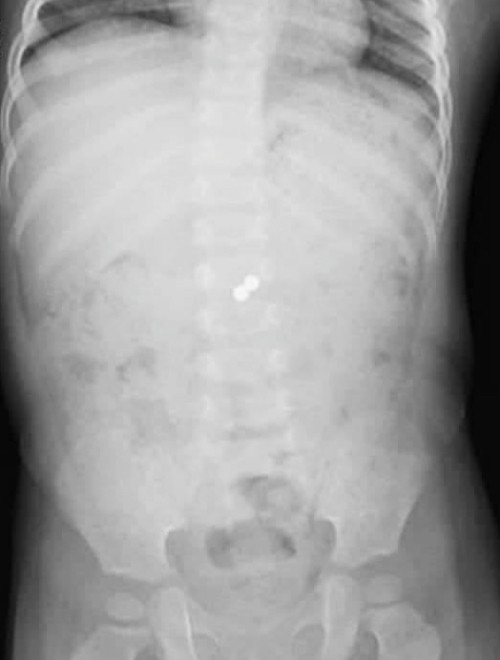

Bé được đưa vào Bệnh viện Nhi đồng Thành phố, các bác sĩ chụp X-quang ngày 24/11 phát hiện hai dị vật tròn nhỏ nằm trong lòng bụng trẻ, khu vực ruột non.

Trong ổ bụng bé, hai viên bi nam châm nằm ở hai khoang ruột khác biệt. Bi không thải ra ngoài theo đường phân mà chúng hít chặt hai đoạn ruột này lại với nhau. Dần dần viên bi xuyên qua thành ruột và bị mạc treo ruột non bao lại, dọa tắc và nguy cơ hoại tử ruột.